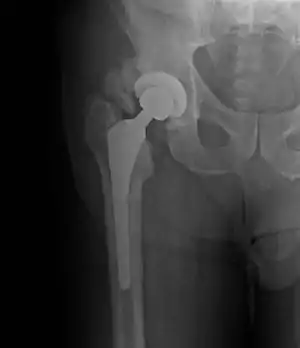

![]() | |

| Heterotopic ossification around the hip joint in a patient who has undergone hip arthroplasty |

Heterotopic ossification of varying severity can be caused by surgery or trauma to the hips and legs. About every third patient who has total hip arthroplasty (joint replacement) or a severe fracture of the long bones of the lower leg will develop heterotopic ossification, but is uncommonly symptomatic. Between 50% and 90% of patients who developed heterotopic ossification following a previous hip arthroplasty will develop additional heterotopic ossification.